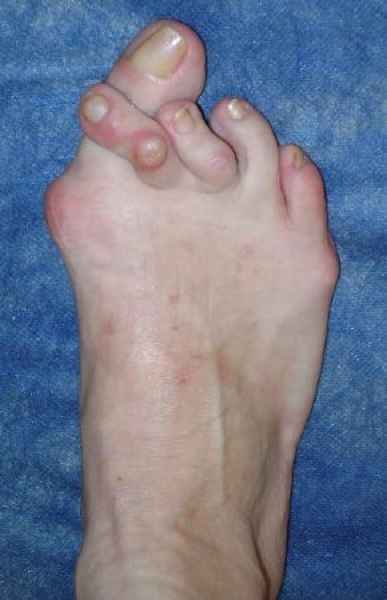

La marcha no solo es característica de la especie humana sino también de cada persona, y más aún varía según el estado de ánimo del momento. Una patología en los pies, se traduce en el rostro, en el ánimo, en el psiquismo. No sólo el dolor produce estos efectos, también un pie deformado o poco estético. En nuestra sociedad, la estética constituye un valor muy apreciado y estas alteraciones causan vergüenza fundamentalmente en las mujeres, que esconden en la playa sus pies en la arena y no pueden usar calzados elegantes.

Tanto la estructura del pie como su funcionalismo que es la marcha, pueden ser asiento y manifestación respectivamente de alteraciones locales ó sistémicas, por lo que su cuidadoso examen resulta de extrema utilidad diagnóstica.